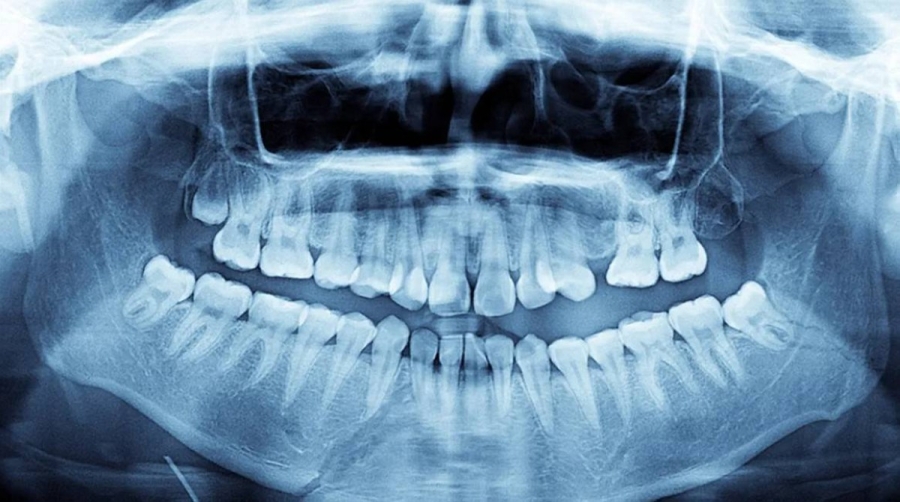

اكتشف مونياندي أسنانه الزائدة لأول مرة أثناء وجبة عائلية في عام 2021، وقال لموسوعة غينيس: "أحصينا الأسنان ووجدنا أن لديّ 38 سناً، وأظهرت صور الأشعة لاحقاً وجود أربعة أسنان أخرى لم تظهر بعد، وبحلول أوائل 2023، بلغ مجموع أسناني 42 سناً، ولحسن الحظ نمت معظمها بشكل مستقيم ودون مضاعفات" وفق iflscience.

تسمى هذه الحالة فرط الأسنان، وهي حالة نادرة تحدث بين 0.1% و3.8% من الأشخاص.

يوضح طبيب الأسنان أولي جوبس أن سببها عادة وراثي أو خلل في الصفيحة السنية، وهي الخلايا التي تتشكل منها الأسنان أثناء النمو، إذا لم تسبب الأسنان الزائدة مشاكل، يمكن تركها دون تدخل.

لكن قد تؤدي الأسنان الزائدة أحياناً إلى صعوبات في التنظيف، مما يزيد من احتمالية التسوس أو أمراض اللثة، كما قد تؤثر على وظيفة الفك إذا منعت الأسنان من الانطباق بشكل صحيح.

في هذه الحالات المعقدة، يجب التخطيط لخلع الأسنان بعناية فائقة لتجنب الإضرار بعظام الفك، حيث لا يختلف شكل الأسنان الزائدة كثيراً عن الأسنان الطبيعية، ومعظمها غير نابت، مما يجعل إدخالها في تقويم الأسنان أمراً صعباً.